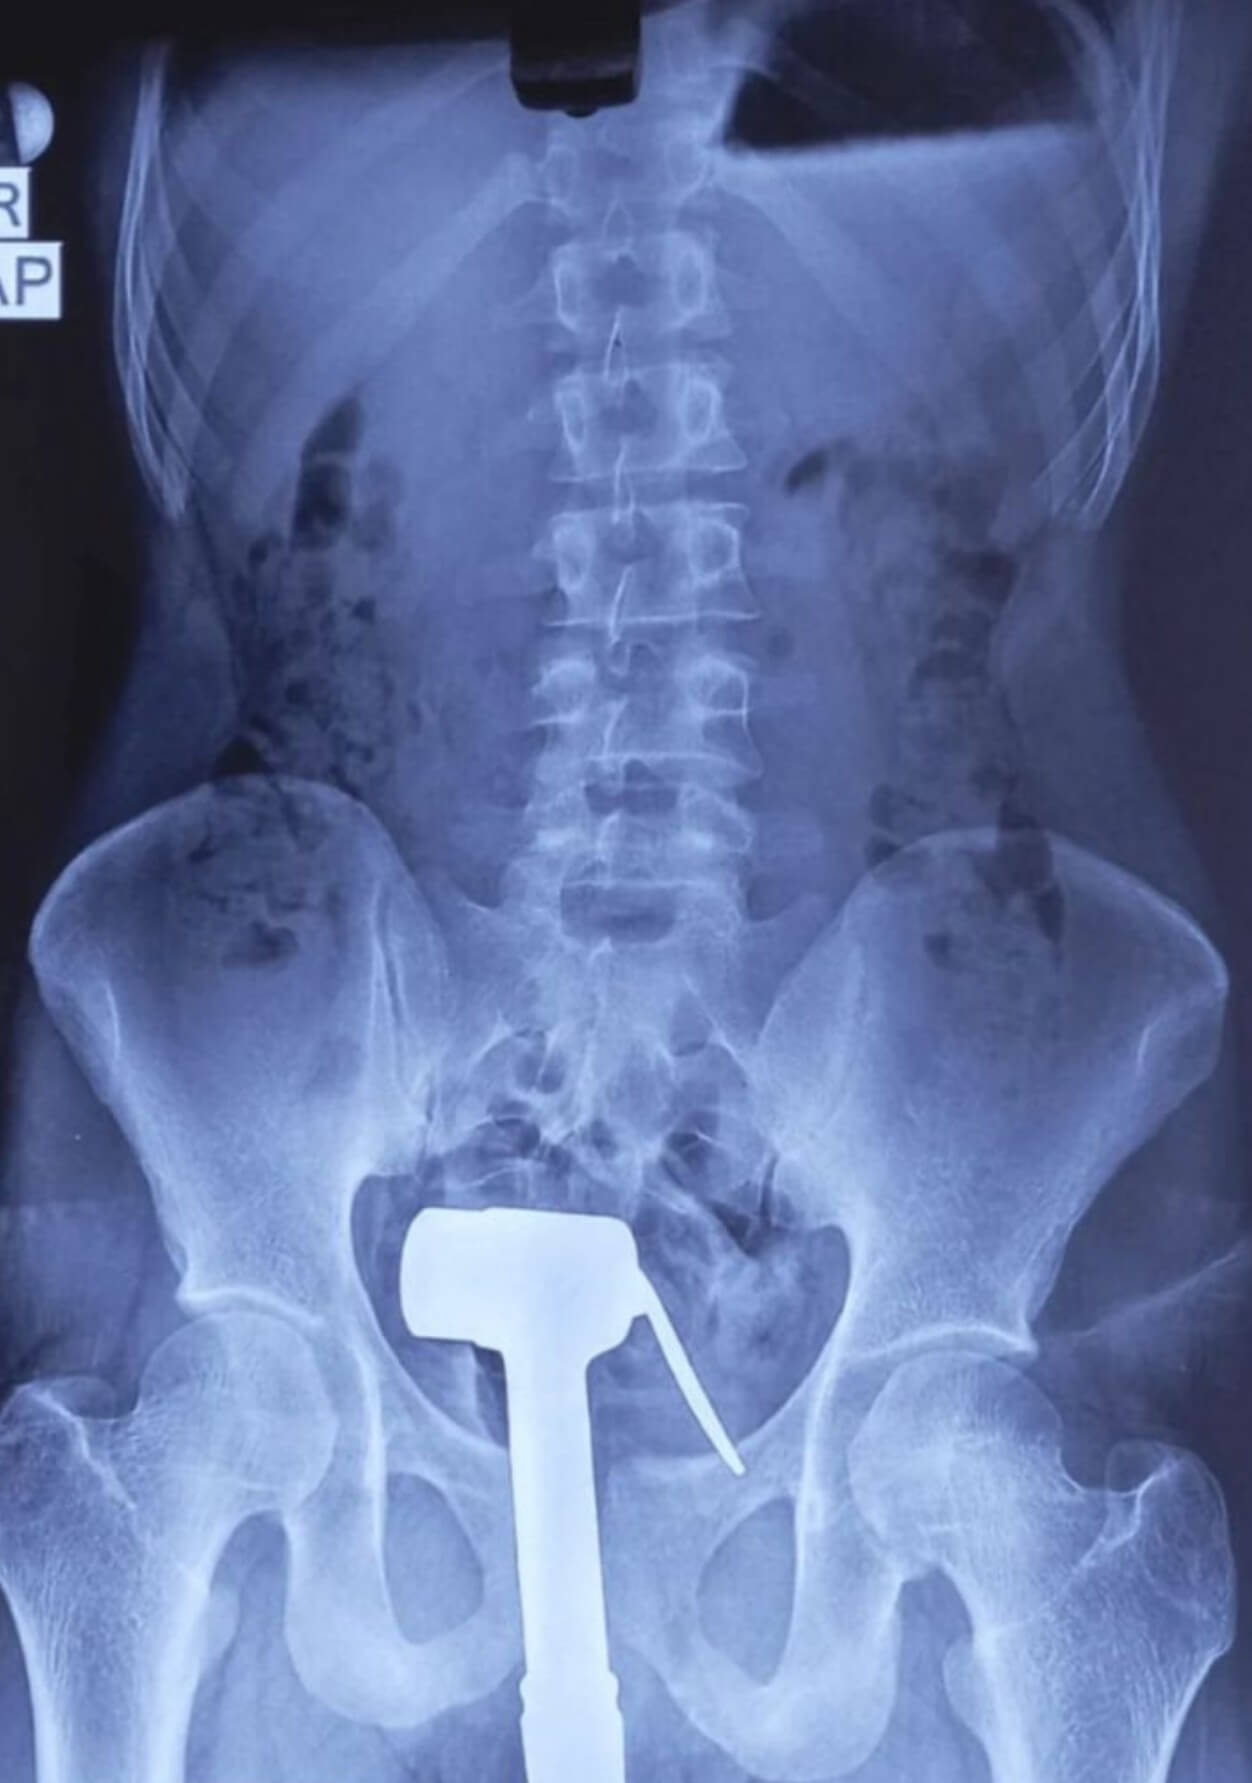

😂😂Sự việc mới đây 1 bệnh nhân Nam vì muốn thử cảm giác lạ khi đang tắm đã tự đưa chiếc vòi xịt vào hậu môn và cái kết thủng trực tràng và ê-kíp bác sĩ 1 phen choáng váng vì độ khủng